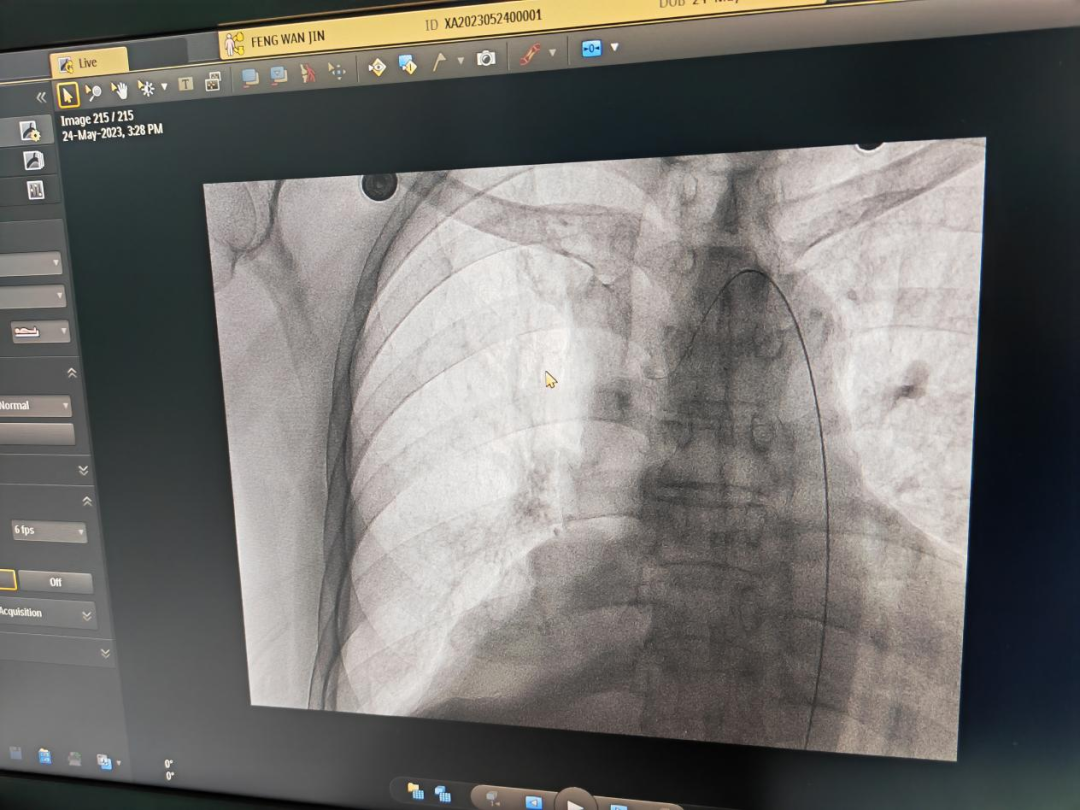

近日,呼吸与危重症医学科顺利开展肺癌的支气管动脉化疗栓塞术,开启了我院肺血管介入诊疗技术的新篇章,也标志着我院肺血管介入诊疗技术迈上了新台阶。

近日,呼吸与危重症医学科联合介入中心、放射影像科等,历时2个多小时,顺利完成手术。

大内科主任、呼吸与危重症医学科主任、主任医师徐峰介绍,支气管动脉化疗栓塞术结合了化疗和微创技术的优势,在治疗中既有对病情精准有效的控制,又有微创技术创伤小、病变部位药物浓度高、疗效好、副作用少、术后恢复快的优点,因此其临床应用疗效逐步得到临床医生及患者的肯定。

术前,专家团队对患者情况进行了详细了解,确定了手术的具体方式。术后,患者安全返回病房,经过严密的监测和护理,患者未出现任何不良反应及并发症。

精准的操作、足够的耐心,扎实的血管解剖知识、高超的介入技术技巧,造就了我院首例支气管动脉化疗栓塞术的成功!经此一役,呼吸与危重症医学科进一步提高了专业技术水平,提升了医疗质量,为我院高质量发展添砖加瓦。